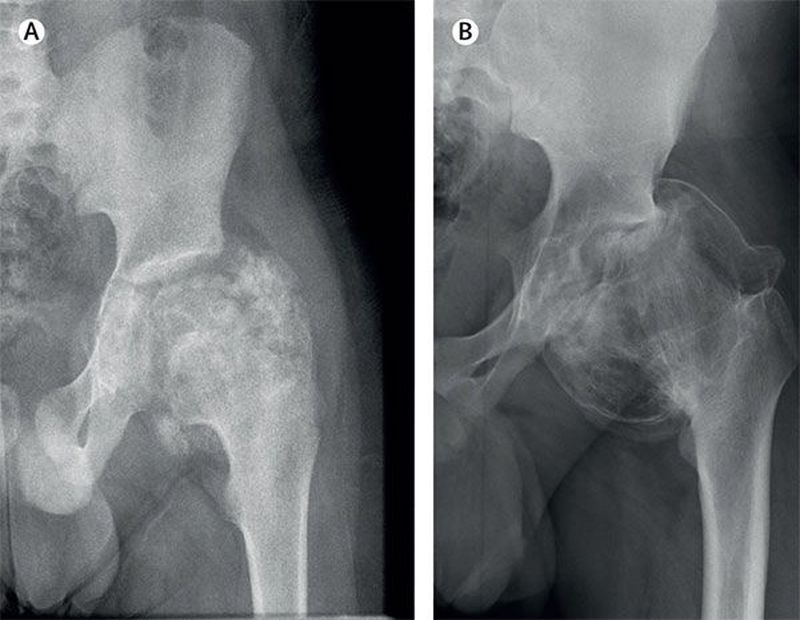

Based on the x-ray, what is the most likely cause of unilateral chronic pain in a 10-year-old boy’s left hip? a) Perthe’s disease b) Septic arthritis c) Chondrosarcoma d) Dysplasia Epiphysealis Hemimelica